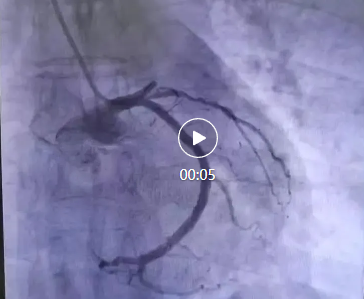

醫(yī)院立即啟動了胸痛中心綠色通道。心血管內(nèi)科李桂武主任、劉興剛主任迅速到位,患者瀕臨崩潰的問道:“大夫,我能活么,孩子?jì)寢岆p目失明,還有倆孩子20歲不到,我要死了,這個家就完了”,李主任、劉主任握著患者的手堅(jiān)定地說道:“我們的目的不僅僅是讓您活著,還要讓您更有質(zhì)量的生活,所以你要堅(jiān)持,相信我們?!彪S即,李主任、劉主任為張先生進(jìn)行了冠狀動脈造影,結(jié)果顯示,張先生的前降支近段完全閉塞,這是導(dǎo)致他胸痛的直接原因。李主任當(dāng)機(jī)立斷,決定進(jìn)行急診冠脈支架植入術(shù)。

手術(shù)過程非常順利。醫(yī)生通過導(dǎo)管將支架送至閉塞部位,成功開通了阻塞的血管,恢復(fù)了心肌的血液供應(yīng)。術(shù)后,張先生的胸痛明顯減輕,呼吸也逐漸平穩(wěn)。被轉(zhuǎn)入心臟重癥監(jiān)護(hù)室(CCU)進(jìn)行密切觀察。醫(yī)生為他制定了詳細(xì)的治療方案,包括抗血小板藥物、他汀類藥物、β受體阻滯劑等,以預(yù)防血栓再形成、穩(wěn)定斑塊并降低心臟負(fù)荷。!